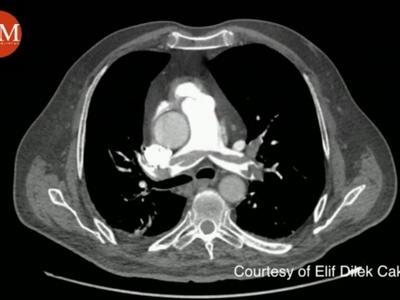

Thoracic aorta

Descending thoracic aorta supplies posterior mediastinum, intercostal arteries, esophagus and bronchi. Aortic aneurysms, traumatic transection and intercostal bleeding are clinically significant in thoracic vascular care.